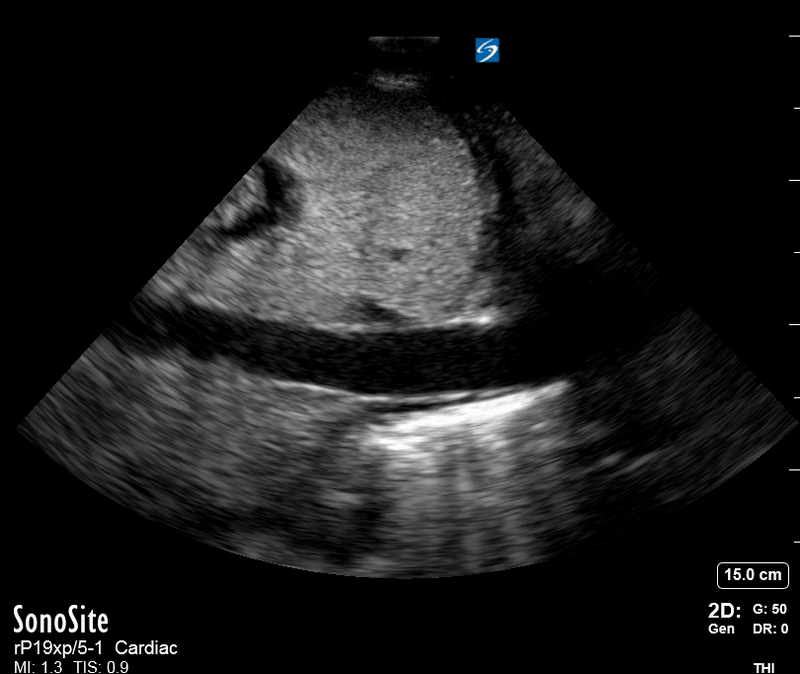

Effusion: is there a pericardial or pleural effusion?

Pericardial effusion is a continuum and can potentially evolve into haemodynamic collapse. Tamponade physiology is detectable earlier with ultrasound than with traditional physical examination, and it has been demonstrated that PoCUS improves mortality in penetrating cardiac trauma. Timely and accurate diagnosis is, therefore, vital.

THE VIEWS

The subxiphoid view is the most reliable for detecting pericardial effusion. Still, it is ideal to obtain different views not to miss a focal effusion as small amounts of fluid can lead to tamponade physiology. Tamponade does not link strictly to the size of the effusion, but correlates more with the speed of onset, causes, and haemodynamic effects.

PITFALLS & PLEURAL EFFUSIONS

A common error is to confuse a pericardial fat pad with effusion. Fatty tissue has a heterogeneous echotexture, moving in coordination with the myocardium, and it cannot be tracked around the heart, especially posteriorly and to the apex. Another pitfall is misinterpreting a pleural effusion as a pericardial effusion. However, they can be differentiated by their relationship to the descending aorta. Pericardial effusion may be seen between the aorta and the LV free wall, whereas pleural effusions are posterior to the descending aorta. Lastly, other causes, namely hypovolaemia and large pleural effusions, can cause RA and RV collapse.